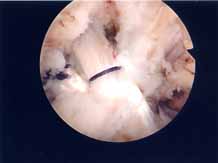

第1段階軟骨形成術

軟骨障害は最初亀裂または剥離で始まります。この状態が第一段階軟骨障害です。このことはあまり一般に知られていません。この最初の亀裂や剥離状態のうちに対処することが最も結果が良好となります。亀裂や剥離が進んでしまうと②の状態になります。